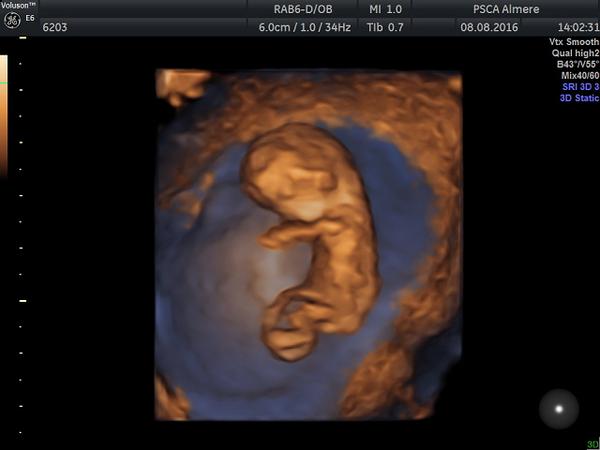

Ahojte. Tak som dnes zbehla k doktorovi a potvrdil mi tehotenstvo 🙂 Bubáčik má 1,6 cm, srdiečko bije. Čo je ale čudné, že vyšiel vek na 7tt+6 a nie 8tt+6 ako mám podľa MS. Keďže presne viem, kedy sme malého zarobili (na 100%) tak viem, že ten údaj podľa MS musí byť správny a teda termín mám mať 13.3. a nie 21.3. ako mi napísali do knižky. Ale neva, buď to doženieme, alebo to bude drobec 😉 Pokúsila som sa vložiť foto cez mobil, ale nechce mi tú fotku pridať, nechápem v čom je zas problém. Skúsim ešte neskôr